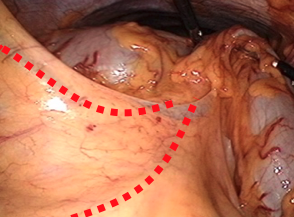

大腸がんは下のような大腸造影検査(注腸検査)、大腸カメラ(大腸内視鏡検査)にて発見、確認することができます。病変の場所、進行の程度により、腸を切る場所や範囲が変わってきます。

S状結腸という場所にできた大腸がんです。がんのために、腸が狭くなっています

大腸疾患に対する腹腔鏡手術は胆嚢摘出術に次いで、一般化している腹腔鏡手術のひとつです。まずは左側の大腸を切る手術から見てみましょう。